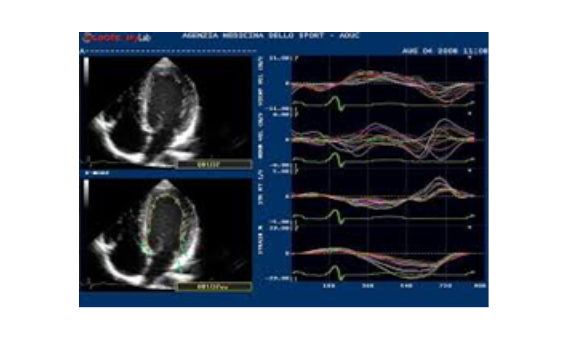

2. Siêu âm tim kiểu TM (Còn gọi là M mode)

Vì tim vận động liên tục theo chu kỳ tâm thu và tâm trương, các van tim cũng vậy, nên khi quét chùm tia siêu âm đi qua 1 thành phần giải phẫu của tim theo 1 vận tốc nhất định, ta sẽ thu được hình ảnh của thành phần đó có dạng sóng. Với kiểu TM, do định vị được các thời điểm trong chu chuyển tim: tâm thu, cuối tâm thu, tâm trương, cuối tâm trương nên việc đo các kích thước và chức năng co bóp của tim rất chính xác. Các lát cắt chủ yếu trong siêu âm tim M mode là lát cắt trục dọc cạnh ức trái..., dựa trên hình ảnh 2D, trục ngang cạnh ức trái, dịch chuyển thanh định hướng (cursor) tới vị trí cần khảo sát để thu được hình ảnh tim mạch.

Siêu âm tim kiểu TM, lát cắt trục dọc cạnh ức trái, cursor ỏ sát đầu tận cùng van hai lá, đo được đường kính thất trái cuối tâm trương (LVIDd), đường kính thất trái cuối tâm thu (LVIDs), qua đó tính chức năng tâm thu thất trái (EF). Ngoài ra còn đo được kích thước thất phải, độ dày của thành thất trái ở tâm trương (IVSd và LVPWd) và tâm thu (IVSs và LVPWs).